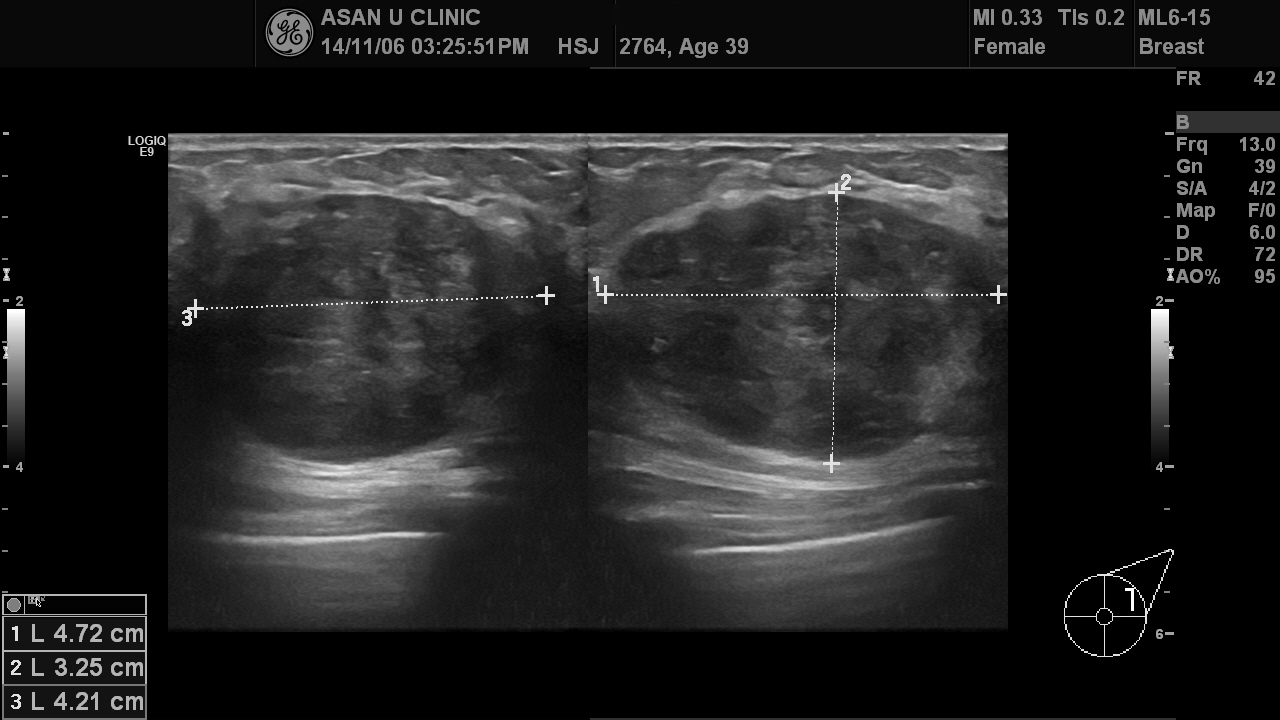

왼쪽 유방에 만져지는 몽우리로 내원한 39세 여성입니다.

본원 초음파 영상으로 본 혹은 4.7cm직경을 가지고 있었으며,